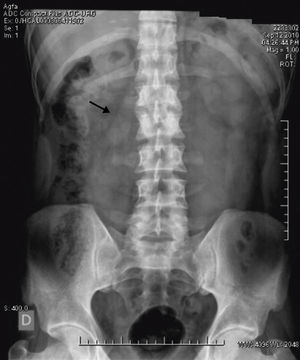

En urgencias, se practicó analítica con hemograma, coagulación, glucosa, urea, creatinina, iones, perfil hepático, lípídico y renal dentro de parámetros normales. Asimismo no se encontraron elevaciones de reactantes de fase aguda y con parámetros nutricionales dentro de límites normales. La radiografía de abdomen demostró borramiento de la línea del psoas izquierdo (fig. 1).